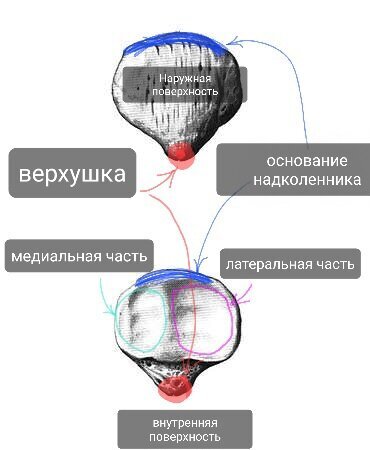

Хорошая картинка с изображением большеберцовой кости со всех сторон, в т.ч. сверху и снизу. Из интернета.

Проксимальный эпифиз сформирован медиальным и латеральным мыщелками, на которых расположены суставные поверхности, образующие большеберцовую часть коленного сустава. Между суставными поверхностями есть костные площадки - переднее и заднее межмыщелковые поля, к которым крепятся передняя и задняя крестообразные связки соответственно (внутренние связки коленного сустава).

В области медиального мыщелка находится точка крепления полуперепончатой мышцы.

Сбоку латерального мыщелка находится суставная поверхность проксимального (верхнего) межберцового сочленения (сустав с малоберцовой костью).

На задней поверхности зпифиза находится точка крепления подколенной мышцы.

По передней поверхности посередине, под мыщелками находится бугристость большеберцовой кости - костный ориентир, точка опоры (при опоре на колено), а также точка крепления одного из крупнейших сухожилий - собственной связки надколенника, также с медиальной стороны к ней подходит общее сухожилие полусухожильной, тонкой и портняжной мышц (так называемая гусиная лапка, о которой много знают те, у кого были травмы коленного сустава). С этой бугристостью связано немало проблем у юных спортсменов, об этом будет статья.

Важные элементы большеберцовой кости.

Передняя поверхность большеберцовой кости - гребень. Очень хорошо прощупывается под кожей. Кто хоть раз ударялся этим местом отлично помнит это место.

Нижний эпифиз сформировон медиальной лодыжкой - тоже костный ориентир. Косточка с внутренней стороны голеностопного сустава. Этим местом тоже больно ударяться, и тут может быть перелом или ушиб (при подворачивании стопы).

К медиальной лодыжке крепятся медиальная группа связок надтаранного сустава (дельтавидные связки).

С внутренней стороны располагается суставная поверхность дистального (нижнего) межберцового сочленения.

Нижняя плоскость большеберцовой кости - суставная поверхность надтаранного чустава. В этом месте осевая нагрузка с таранной кости почти полностью передаётся на большеберцовую.